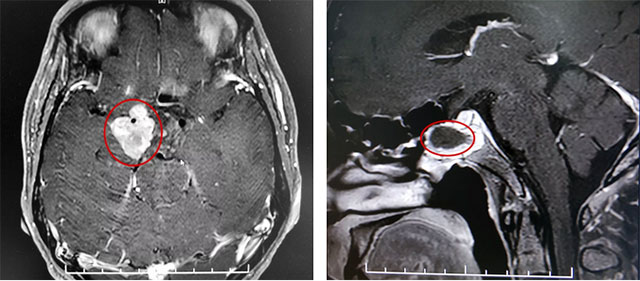

▲ 巨大垂体瘤残余

患者蔡先生(化名)因持续头痛、视力下降被查出是垂体无功能巨大腺瘤,肿瘤大小超过3cm。在杭州一家医院做了经蝶窦垂体瘤切除手术后,由于术后肿瘤残余较多,出现头痛情况,视力较术前未见明显改观,左侧视力0.12,右侧视力0.1。后慕名来到上海蓝十字脑科医院。

李士其教授指出,经鼻蝶手术主要用于肿瘤位于鞍内者,对于鞍内、鞍上均有生长的巨大垂体瘤,考虑联合入路手术,部分患者也可以考虑多次经鼻蝶手术。

该巨大垂体腺瘤患者鞍上区域残余肿瘤偏向右侧,只能通过开颅手术切除。

在充分准备并征得家属同意后,李士其教授在吴治群博士、黄秀夫医生协助下为患者行开颅手术,经翼点入路将残余约2.5cm*2cm*2cm大小肿瘤切除。